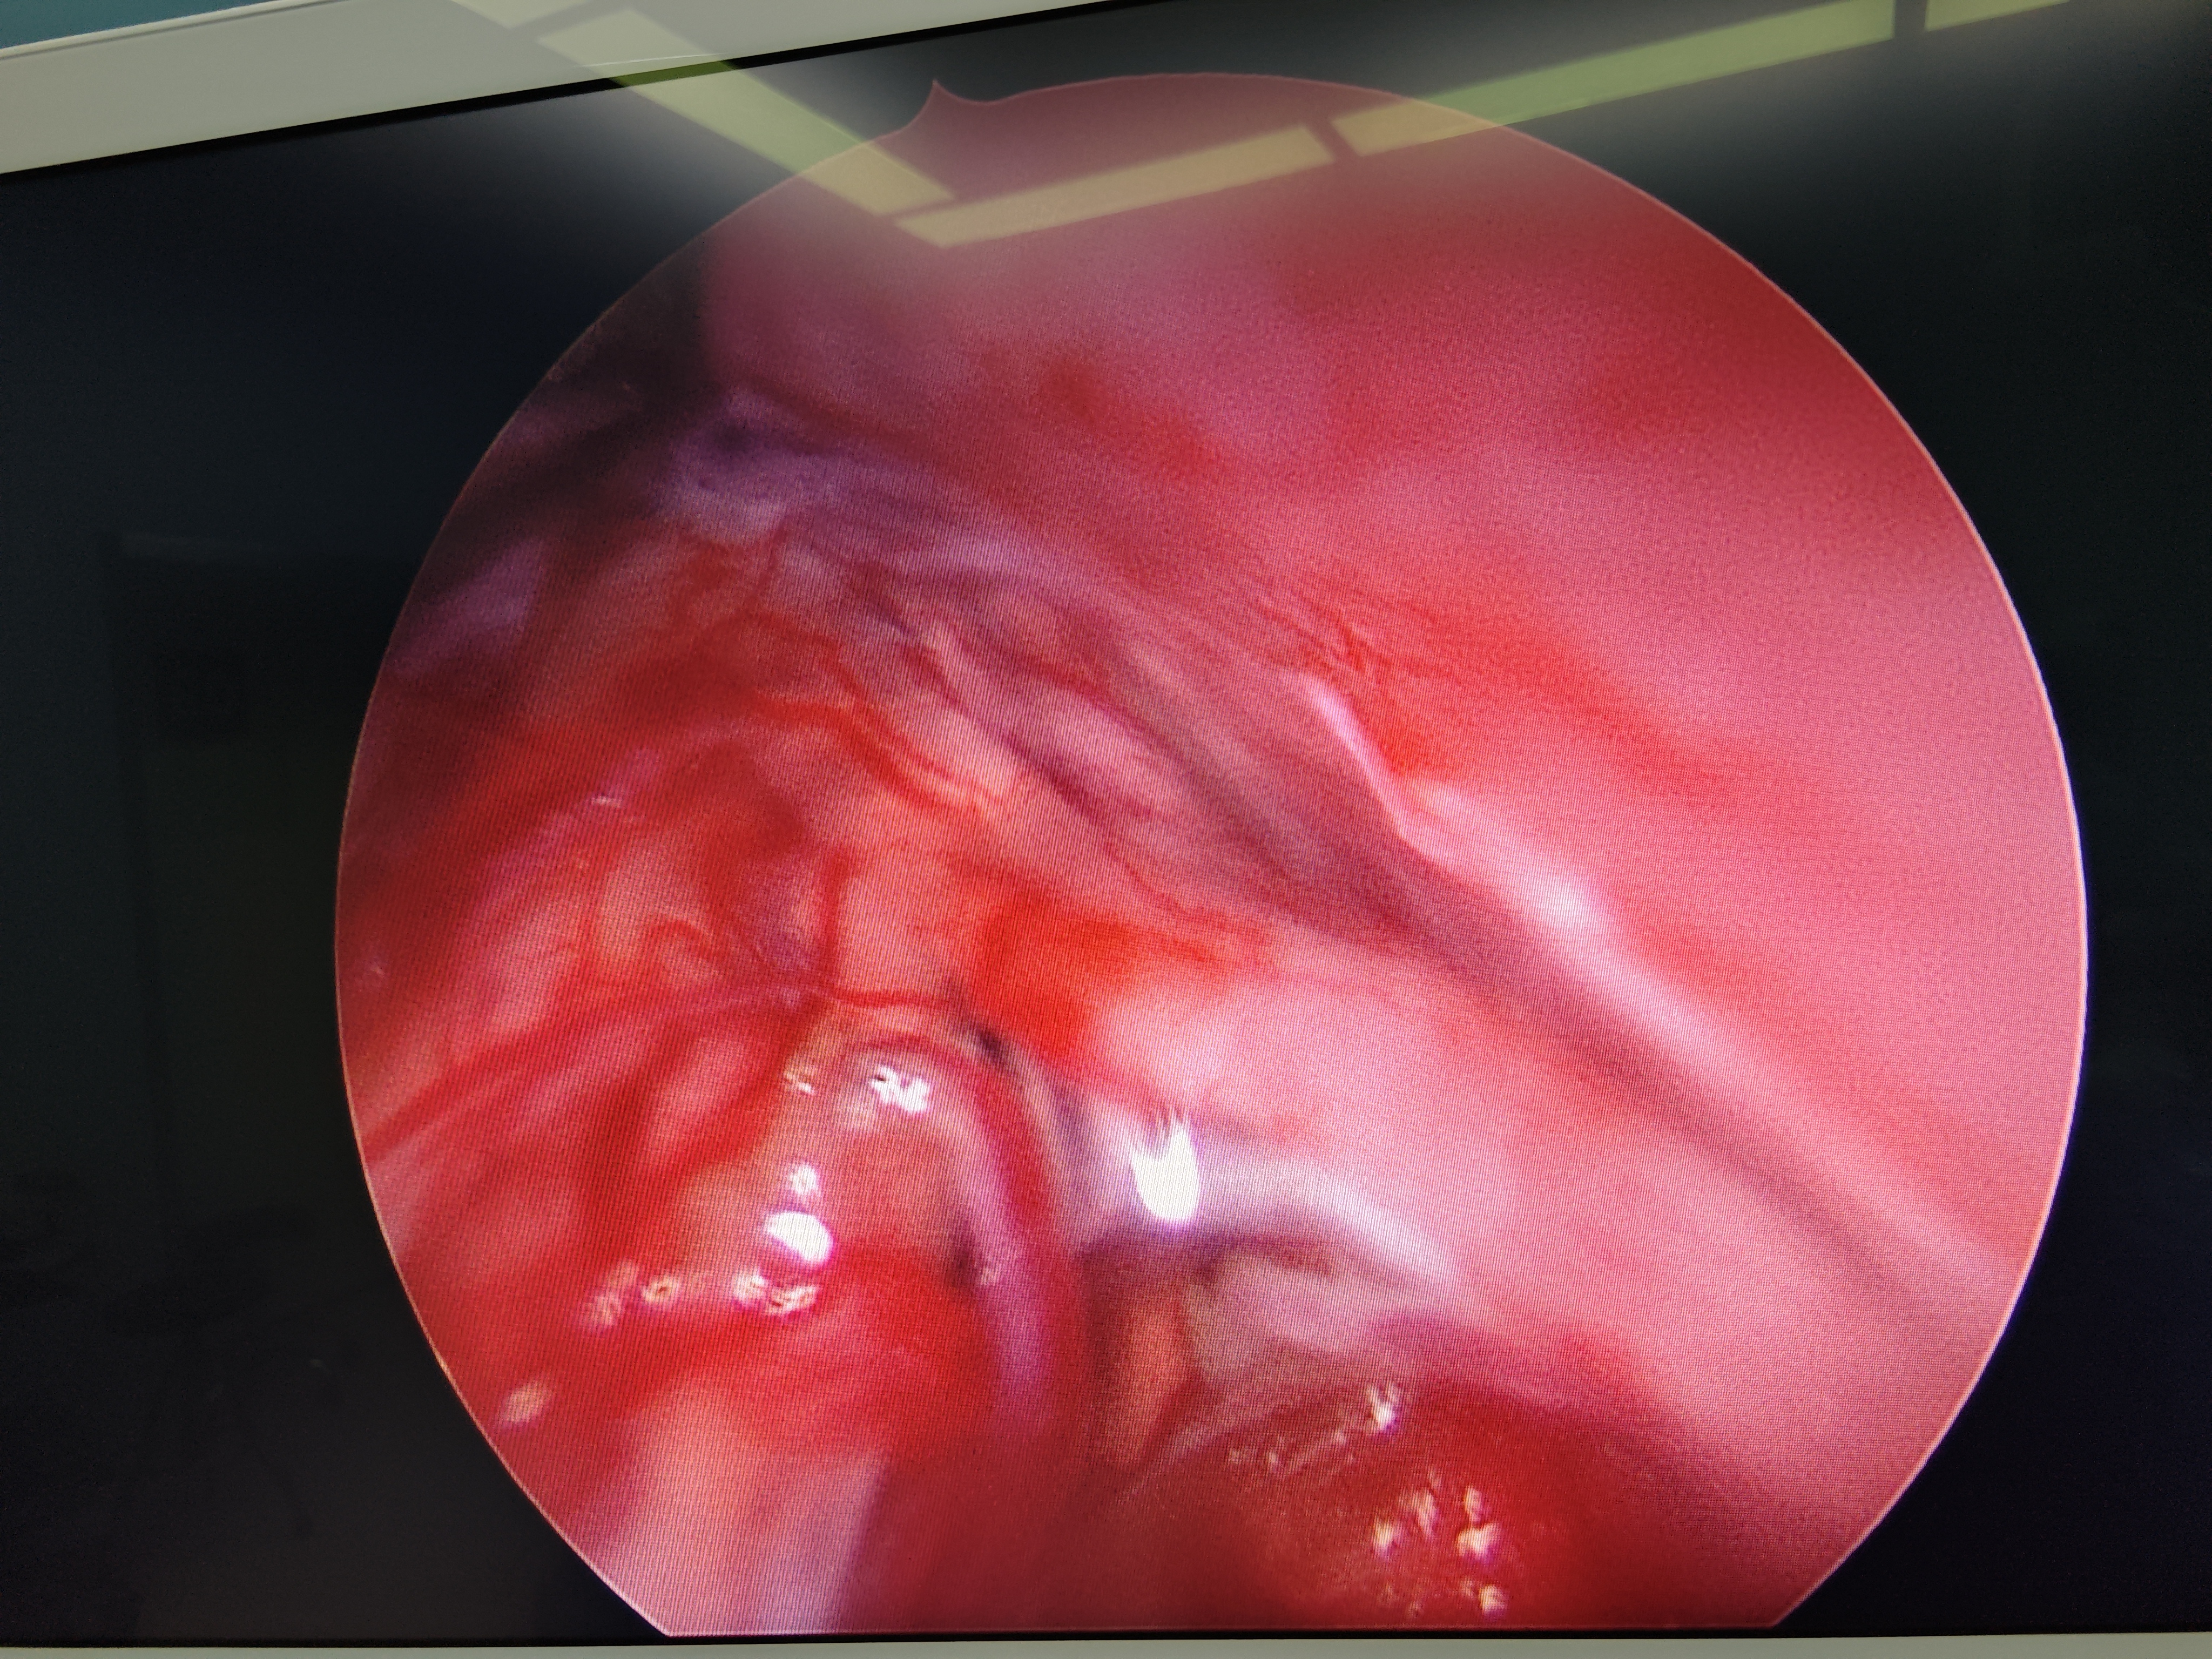

脊髓脊柱-脊髓脊柱肿瘤

神经纤维瘤病的治疗需要综合考虑患者的病情、症状、年龄、身体状况等因素,制定个性化的治疗方案。